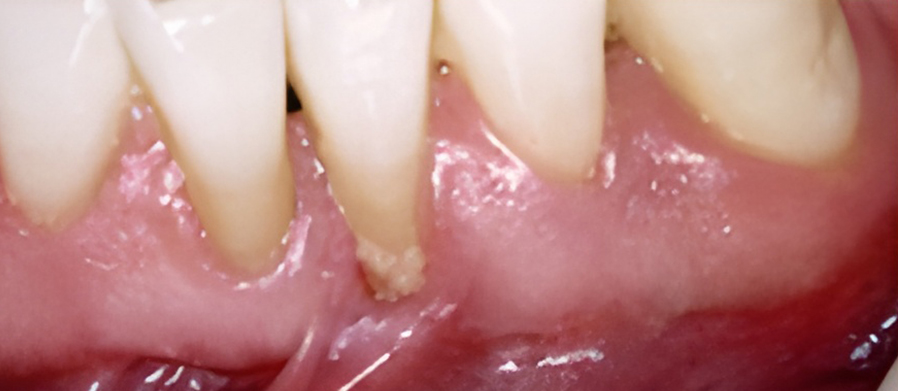

잇몸이 심하게 붓고 피가 자주 나며 치가가 흔들리기도 합니다. 치아 뿌리가 드러나기도 하며 때로는 잇몸에 고름이 나와 음식물을 잘 씹을 수가 없습니다.

잇몸에 고름이 차 있다면 배농이 필요하고, 잇몸을 절개해서 염증조직을 제거하거나 치은이나 뼈를 이식하는 수술을 시행하기도 합니다.

치아 내부 신경이 감염되면 뿌리 끝에 고름이 차는 농양이 생길 수 있습니다. 이로 인해 심한 통증, 부기, 씹기 불편 등이 나타나며 신속한 치료가 필요합니다.